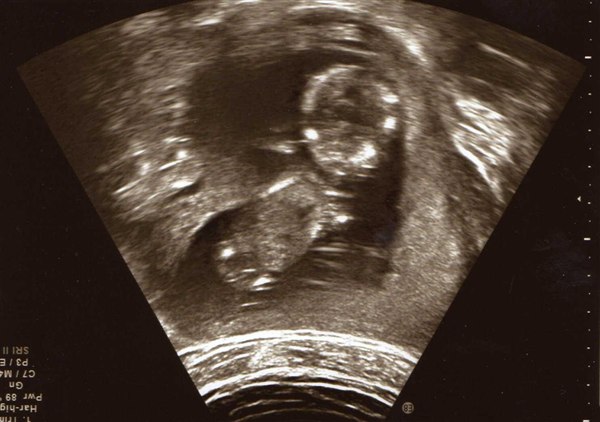

Så er dagen kommet hvor vi skal til kønsscanning og se om lille-niv er en lille pige eller lille dreng

Nu har der været nogle gæt omkring kønnet, og så tænkte jeg at jeg da kunne lave en lille gætte leg ud af det - så derfor har jeg sat billeder ind af lille-niv fra NF scanning og af min mave idag.

Vedhæftede fotos (klik for at se i fuld størrelse)